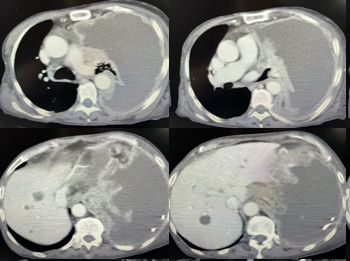

胸部CT如下图:

从上图CT可以看到,患者左侧大量胸水,即使引流了2L,似乎胸水并没有丝毫减少,左肺压缩只剩下很小一部分,纵隔也有向右侧推移的表现。仔细看还可以发现左侧胸膜有增厚。